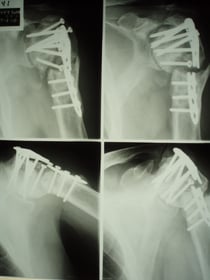

○鎖骨骨折(病院で手術)

病院で手術を受けました。 鎖骨に金属のプレートを取り付ける固定をしました。

一年以上たっても肩が水平にも挙げられず痛みと不自由な生活を強いられ当院に相談に来られました。

病院では特にリハビリもなく自分でよく動かしなさいと指示があったそうです。

週に2回 温熱療法と医療マッサージを施し、同時に筋力強化により、

現在では肩が挙がるようになり仕事にも支障がなくなりました。